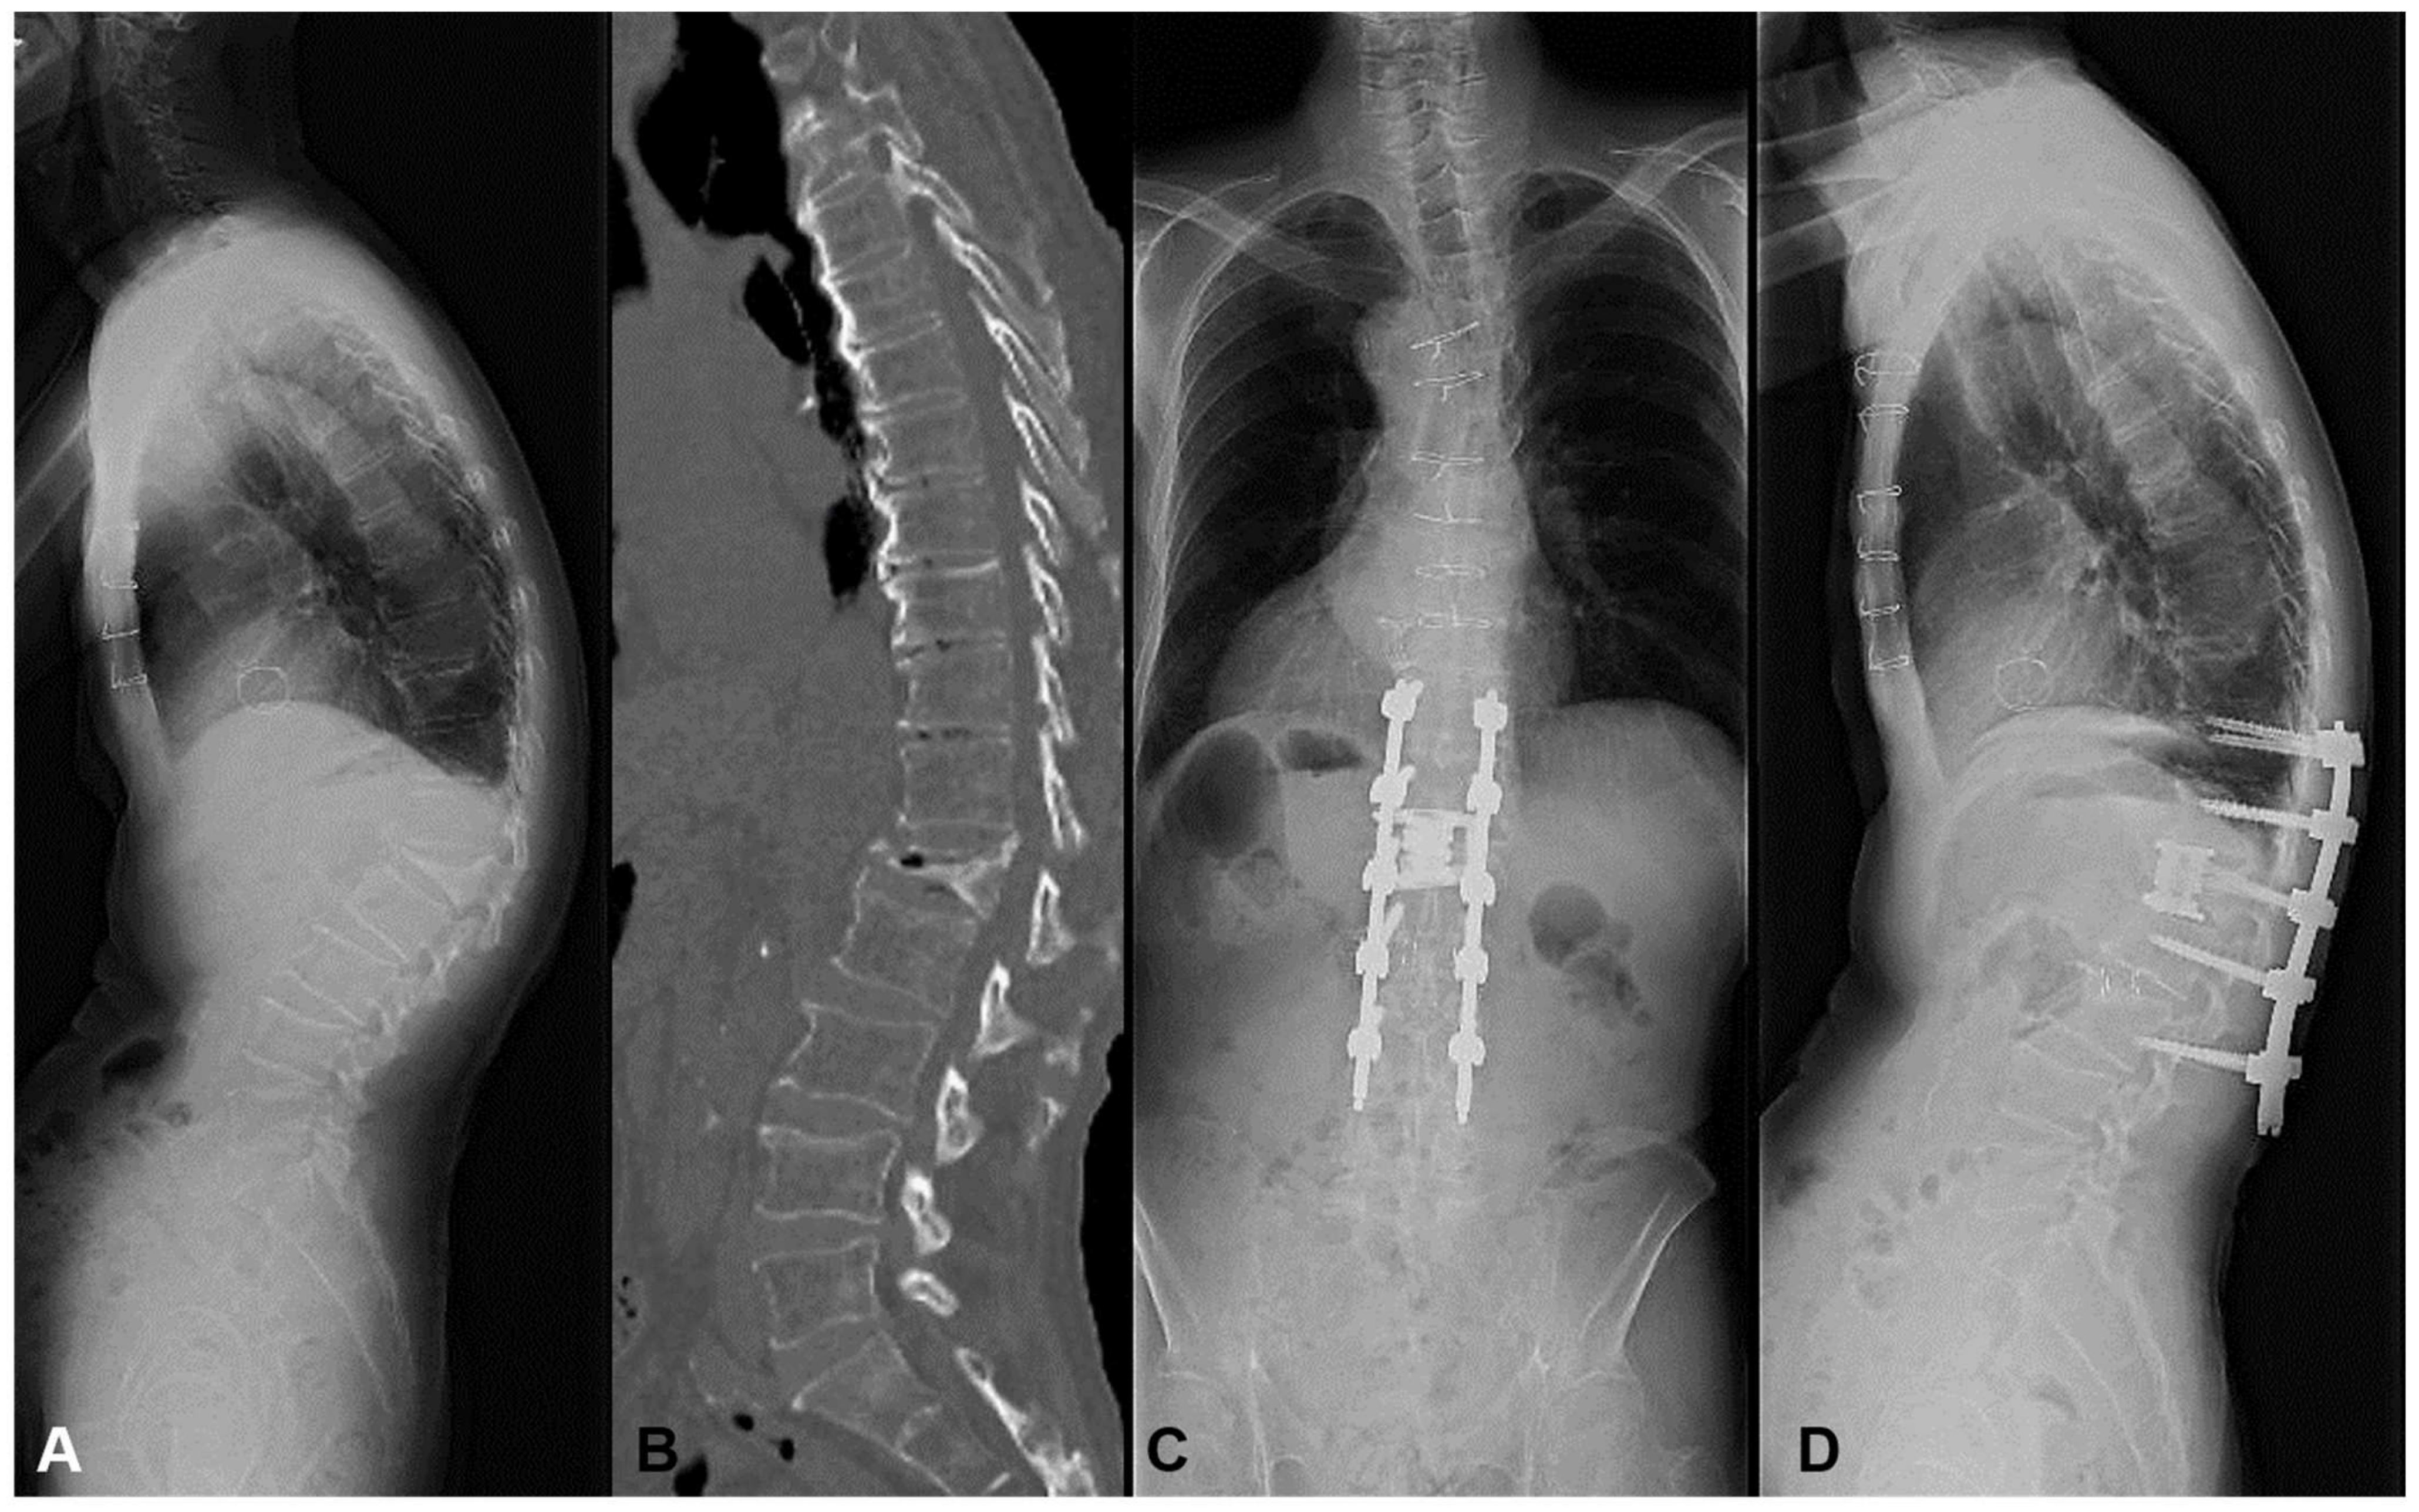

3.1.3. Case 3: 78 Years Old, Female, L4 Vertebral Collapse

The patient suffered from L4 compression fracture 4 months ago. The gait disturbance progressed with the weakness of lower extremities due to neural compression of vertebral collapse. The MIS L4 corpectomy followed by percutaneous screw fixation was conducted, resulting in the recovery of motor loss and gait disturbance. (Figure 6) In this case, we conducted short-segment fusion because of no LK and low PI of 42 degrees. After surgery, the LK was zero degrees with a postoperative mismatch of 30 degrees. These values were within our obtained threshold of 40 degrees, leading to no MC.

Figure 6.

A 78-year-old female suffering from L4 vertebral collapse. The MIS L4 corpectomy followed by percutaneous screw fixation was conducted, resulting in the recovery of motor loss and gait disturbance without mechanical complications. (A) Preoperative lateral X-ray, (B) Preoperative myelogram CT, (C) Standing AP X-ray at one year postoperatively, (D) Standing lateral X-ray at one year postoperatively.